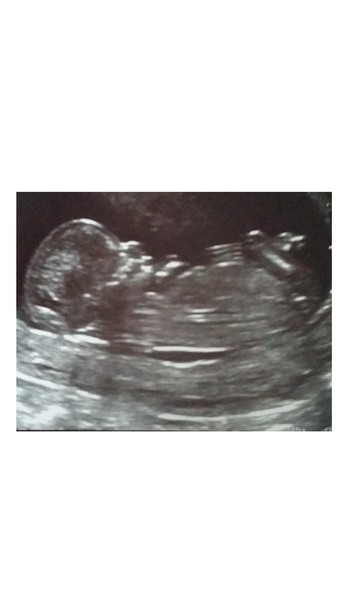

My scan yesterday all seemed to go OK, my dates have been brought forward by 4 days so I'm now due on the 4th Feb. NT was 1.6 mm and I should know about the blood test results next week if I'm high risk.

Poor sleepy bambino had to be woken up by the sonographer (must take after me) and did a big stretch - aaaw!

Here's the pic - the lovely well trained nurse said it had a beautiful shaped head (possibly clutching at straws in terms of dishing out compliments but I'll take it Smile)

Gorgeous picture zebra! He/she does have a lovely shaped head Grin

Lovely pic zebra!

Lovely pic (and head shape!) zebra!

Congratulations zebra ! That is a lovely shaped head. Perfect.